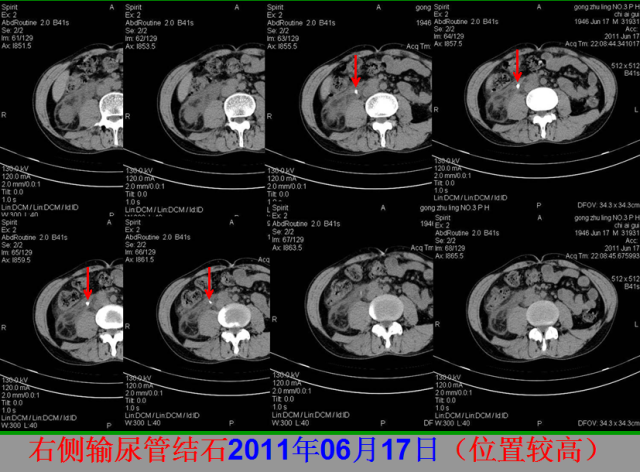

急腹症篇

05